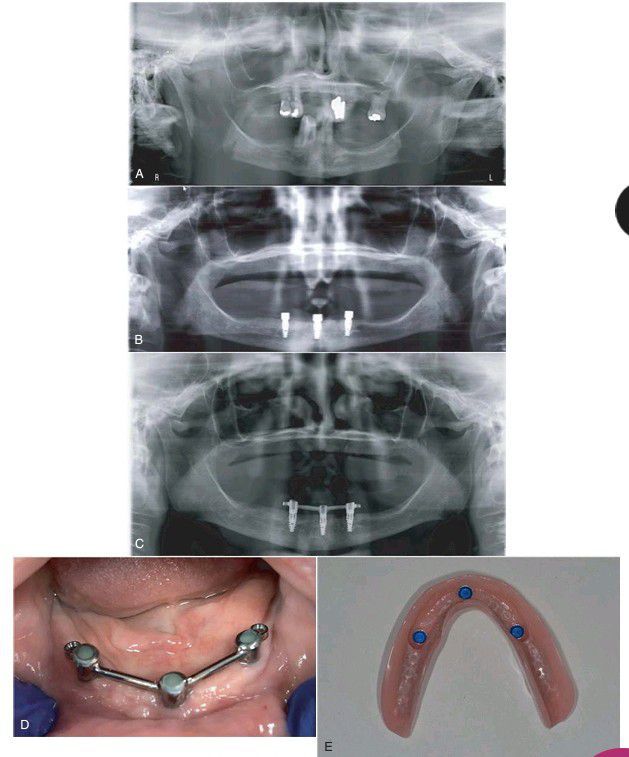

Failed maxillary and mandibular dentition with moderate atrophy of the mandible treated with conventional maxillary denture and mandibular overdenture. (A) Pretreatment Panorex. (B) Placement of three mandibular implants. (C) Panorex of titanium bar splinting three implants. (D) Implant-supported milled titanium bar with attachments. (E) View of the intaglio surface of the metal-reinforced final overdenture with attachments.